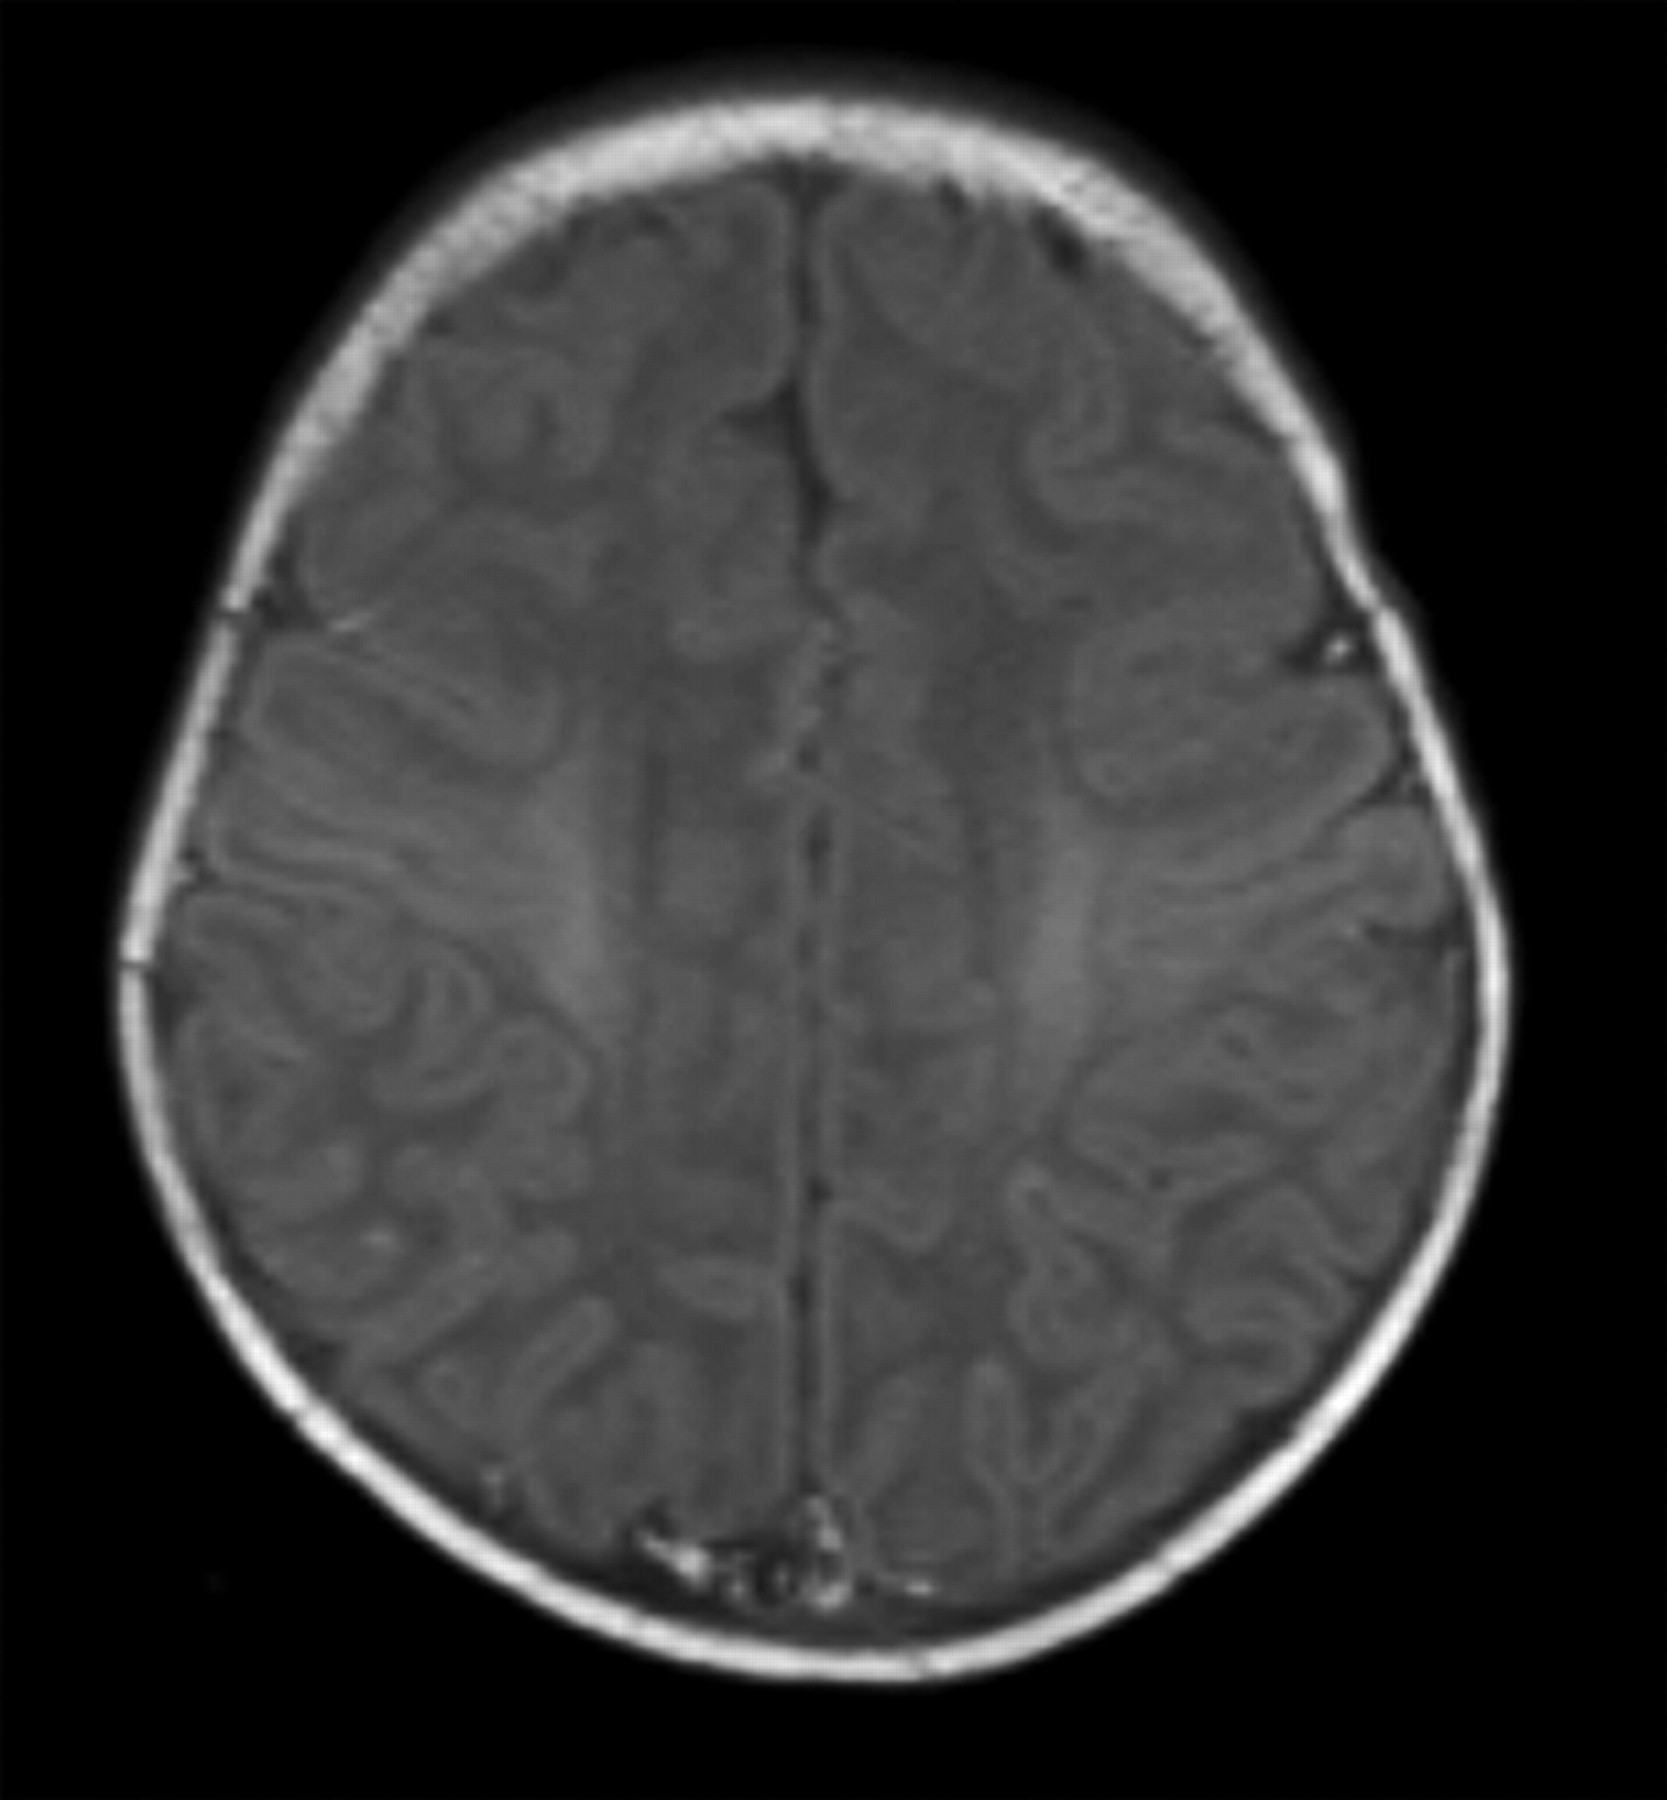

Term-born infant with a small dimple at the back and without neurologic symptoms. T1-weighted image (TR/TE, 640/16; signals acquired, 2; matrix, 205 × 256; section thickness, 5 mm; section gap, 0.5 mm; FOV, 16 cm) of the infant from the control group at 8 days of age. The image shows higher SI in the CR than in the PC. The flow chart predicted the infant to come from the control group.

An infant born at a gestational age of 40+4 weeks with cesarean delivery for fetal distress who had an Apgar score of 0–4–5. Resuscitation was required, and there were no brain stem reflexes. T1-weighted image (TR/TE, 550/14; signals acquired, 2; matrix, 205 × 256; section thickness, 5 mm; section gap, 0.5 mm; FOV, 16 cm) of the infant from the HIE group at 3 days of age. The image shows higher SI in the PP than in the PLIC and abnormal SI in the lateral thalami. The flow chart predicted the infant to come from the HIE group.

Term-born infant of a mother with solutio placentae. T1-weighted image (TR/TE, 550/14; signals acquired, 2; matrix, 205 × 256; section thickness, 5 mm; section gap, 0.5 mm; FOV, 16 cm) of the infant from the HIE group at 10 days of age. The image shows higher SI in the PC than in the CR. T1-weighted imaging also showed (not shown here) equal SI in the PP and the PLIC. The flow chart predicted the infant to come from the HIE group.